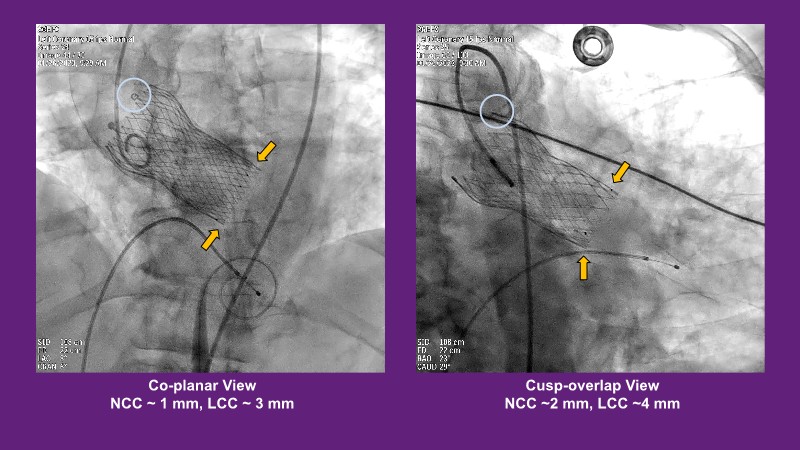

Don’t miss this PCR Tokyo Valves 2025 session replay, where leading experts share key techniques for simplifying and optimising TAVI procedures with the Evolut device. This session covers essential insights into safely performing procedures on patients with various anatomical types using the self-expandable valve, while emphasising the importance of long-term patient care and outcomes. Discover valuable strategies for surgical explantation of transcatheter aortic bioprostheses, coronary cannulation, and commissural alignment post-TAVR. Learn expert tips for streamlining procedures, such as semi-rapid pacing, using Dryseal long, and skipping pre-BAV to improve TAVI results. Watch now to stay ahead in the field!

- To understand how the self-expandable valve can be used to safely perform procedures on patients with various anatomy types

- To understand simple procedure as semi-rapid pacing, using Dryseal long and skip pre-BAV